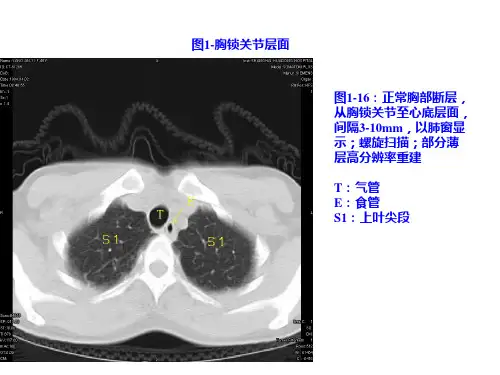

正常胸部CT影像表现

《正常胸部CT读片》PPT课件